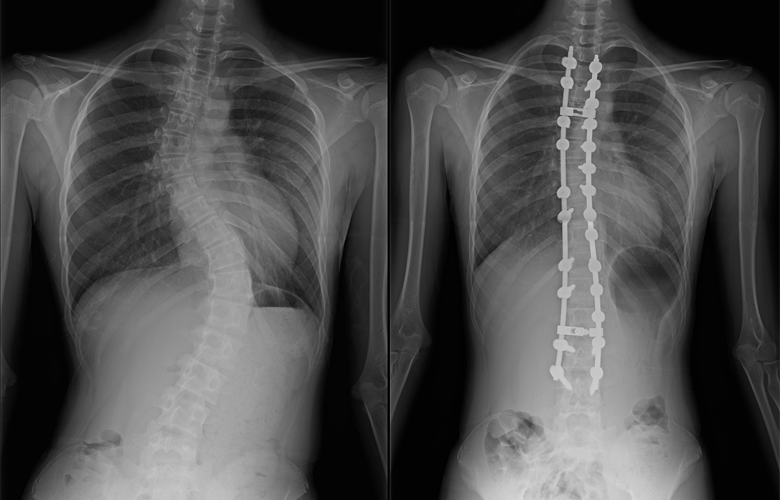

側弯症の手術方法

側弯症の手術方法は、後方矯正固定術(背中から手術する)、前方矯正固定術(お腹側から手術をする)に大別されますが、現在は後方矯正固定術という術式が主流となっています。

後方矯正固定術は、背中の正中部分(真ん中)を切開し、最も傾いている椎体から逆向きに最も傾いている椎体の間にかけて、背骨が見えるように背骨の周囲についている筋肉をはがします。

その後、それぞれの背骨の左右にスクリューを2本ずつ挿入し、それらをロッドと呼ばれるチタン合金やコバルトクロム合金のバーで連結することで側弯を矯正します。各椎体の間にある関節(椎間関節)に、局所の骨や人工骨を移植した後、出血をはじめとする合併症がないことを確認して、傷を閉じます。